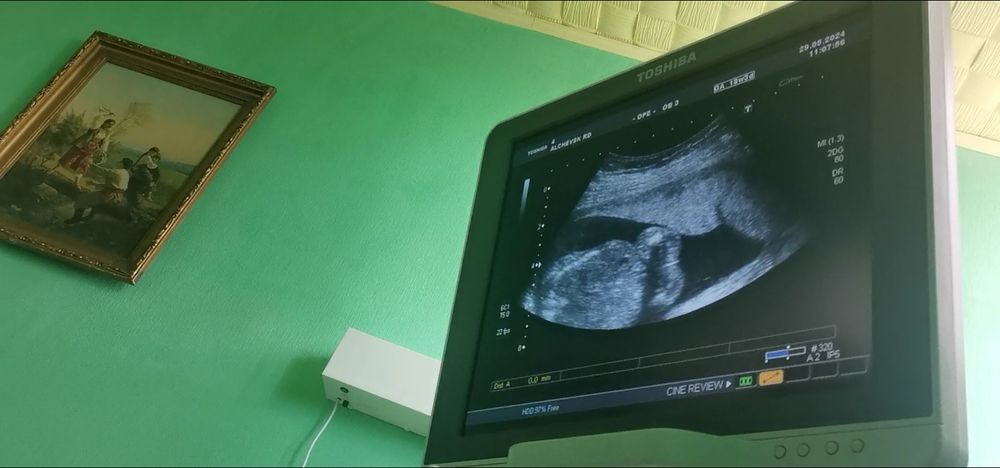

Узи. Кто у нас

Сверху справа это что такое? Как я поняла малыш слева снизу, но какая его часть?)

Теперь нужно смириться с мыслью о сыне 😅 Пол ребёнка